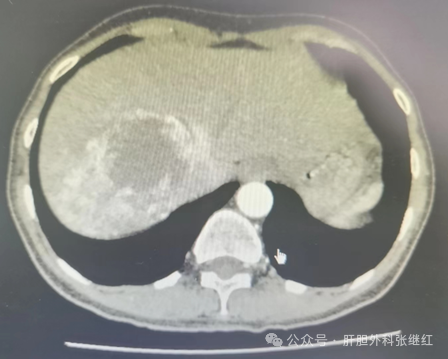

肝血管瘤主要是胚胎发育中血管发育异常所致的血管畸形,是最常见的肝良性肿瘤之一。大多数肝血管瘤生长缓慢,甚至到了一定程度便停止生长,临床上一般在单个直径5Cm以下者,只要不再增长,一般对身体不会构成危害。目前未发现对肝血管有疗效的药物。既往观点认为:肿瘤直径<5cm者,不需手术治疗,定期复查,随诊即可;肿瘤直径5-10cm者,可考虑手术治疗;肿瘤直径>10cm者,一般行手术治疗。然而,肝血管瘤的治疗,特别是手术治疗的指征问题,一直存在较大争议。为了尽可能规范肝血管瘤的诊治,2019年国际肝胆胰协会中国分会制定了《肝血管瘤诊断和治疗多学科专家共识(2019版)》(下文简称共识),将肝血管瘤分为三级三型,并提出了各级各型的治疗原则与方法。

根据肝血管瘤瘤体的大小分为小血管瘤(肿瘤直径<5cm),大血管瘤(肿瘤直径5-10cm)和巨大肝血管瘤(肿瘤直径10cm以上)三级。根据肝血管瘤的数量将其分为3型,各型又根据瘤体大小或肿瘤直径之和或体积之和分为2或3个亚型,即:I型为单发肝血管瘤,肿瘤直径<5cm的为Ia型,肿瘤直径5-10cm为Ib型,肿瘤直径10cm以上为Ic型;II型为多发肝血管瘤,瘤体2-5个,肿瘤直径之和<10cm的IIa型,肿瘤直径之和10-20cm为Ib型,肿瘤直径之和20cm以上为IIc型;III型为弥漫型肝血管瘤,瘤体超过5个,弥漫性分布,瘤体体积之和小于肝体积的50%为IIIa型,瘤体体积之和超过肝体积50%为IIIb型。

肝血管瘤是否需要治疗取决于有无危险因素的存在。危险因素是指肝血管瘤伴有症状、严重并发症、迅速增长或不除外恶变等危及患者健康或可能危及患者健康的因素。对于不伴危险因素的I、II、III型肝血管瘤病人,无论肿瘤大小、位置,原则上以随访观察为主,建议半年或1年复查一次;伴有危险因素的肝血管瘤才需要酌情治疗。对于三级肝血管瘤,一般来说,小血管瘤无症状,不危害身体,不需任何治疗,随访观察即可;大血管瘤和巨大血管瘤伴有危险因素才需酌情治疗。